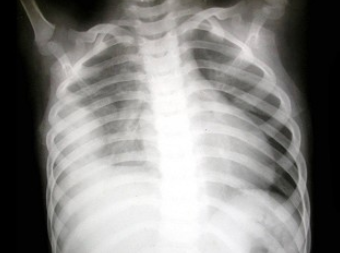

患儿,男,1天,生后呼吸困难,有窒息史,如图,最可能的诊断为()

A.新生儿肺炎

B.新生儿湿肺

C.新生儿肺出血

D.新生儿呼吸窘迫综合症

E.胎粪吸入综合征